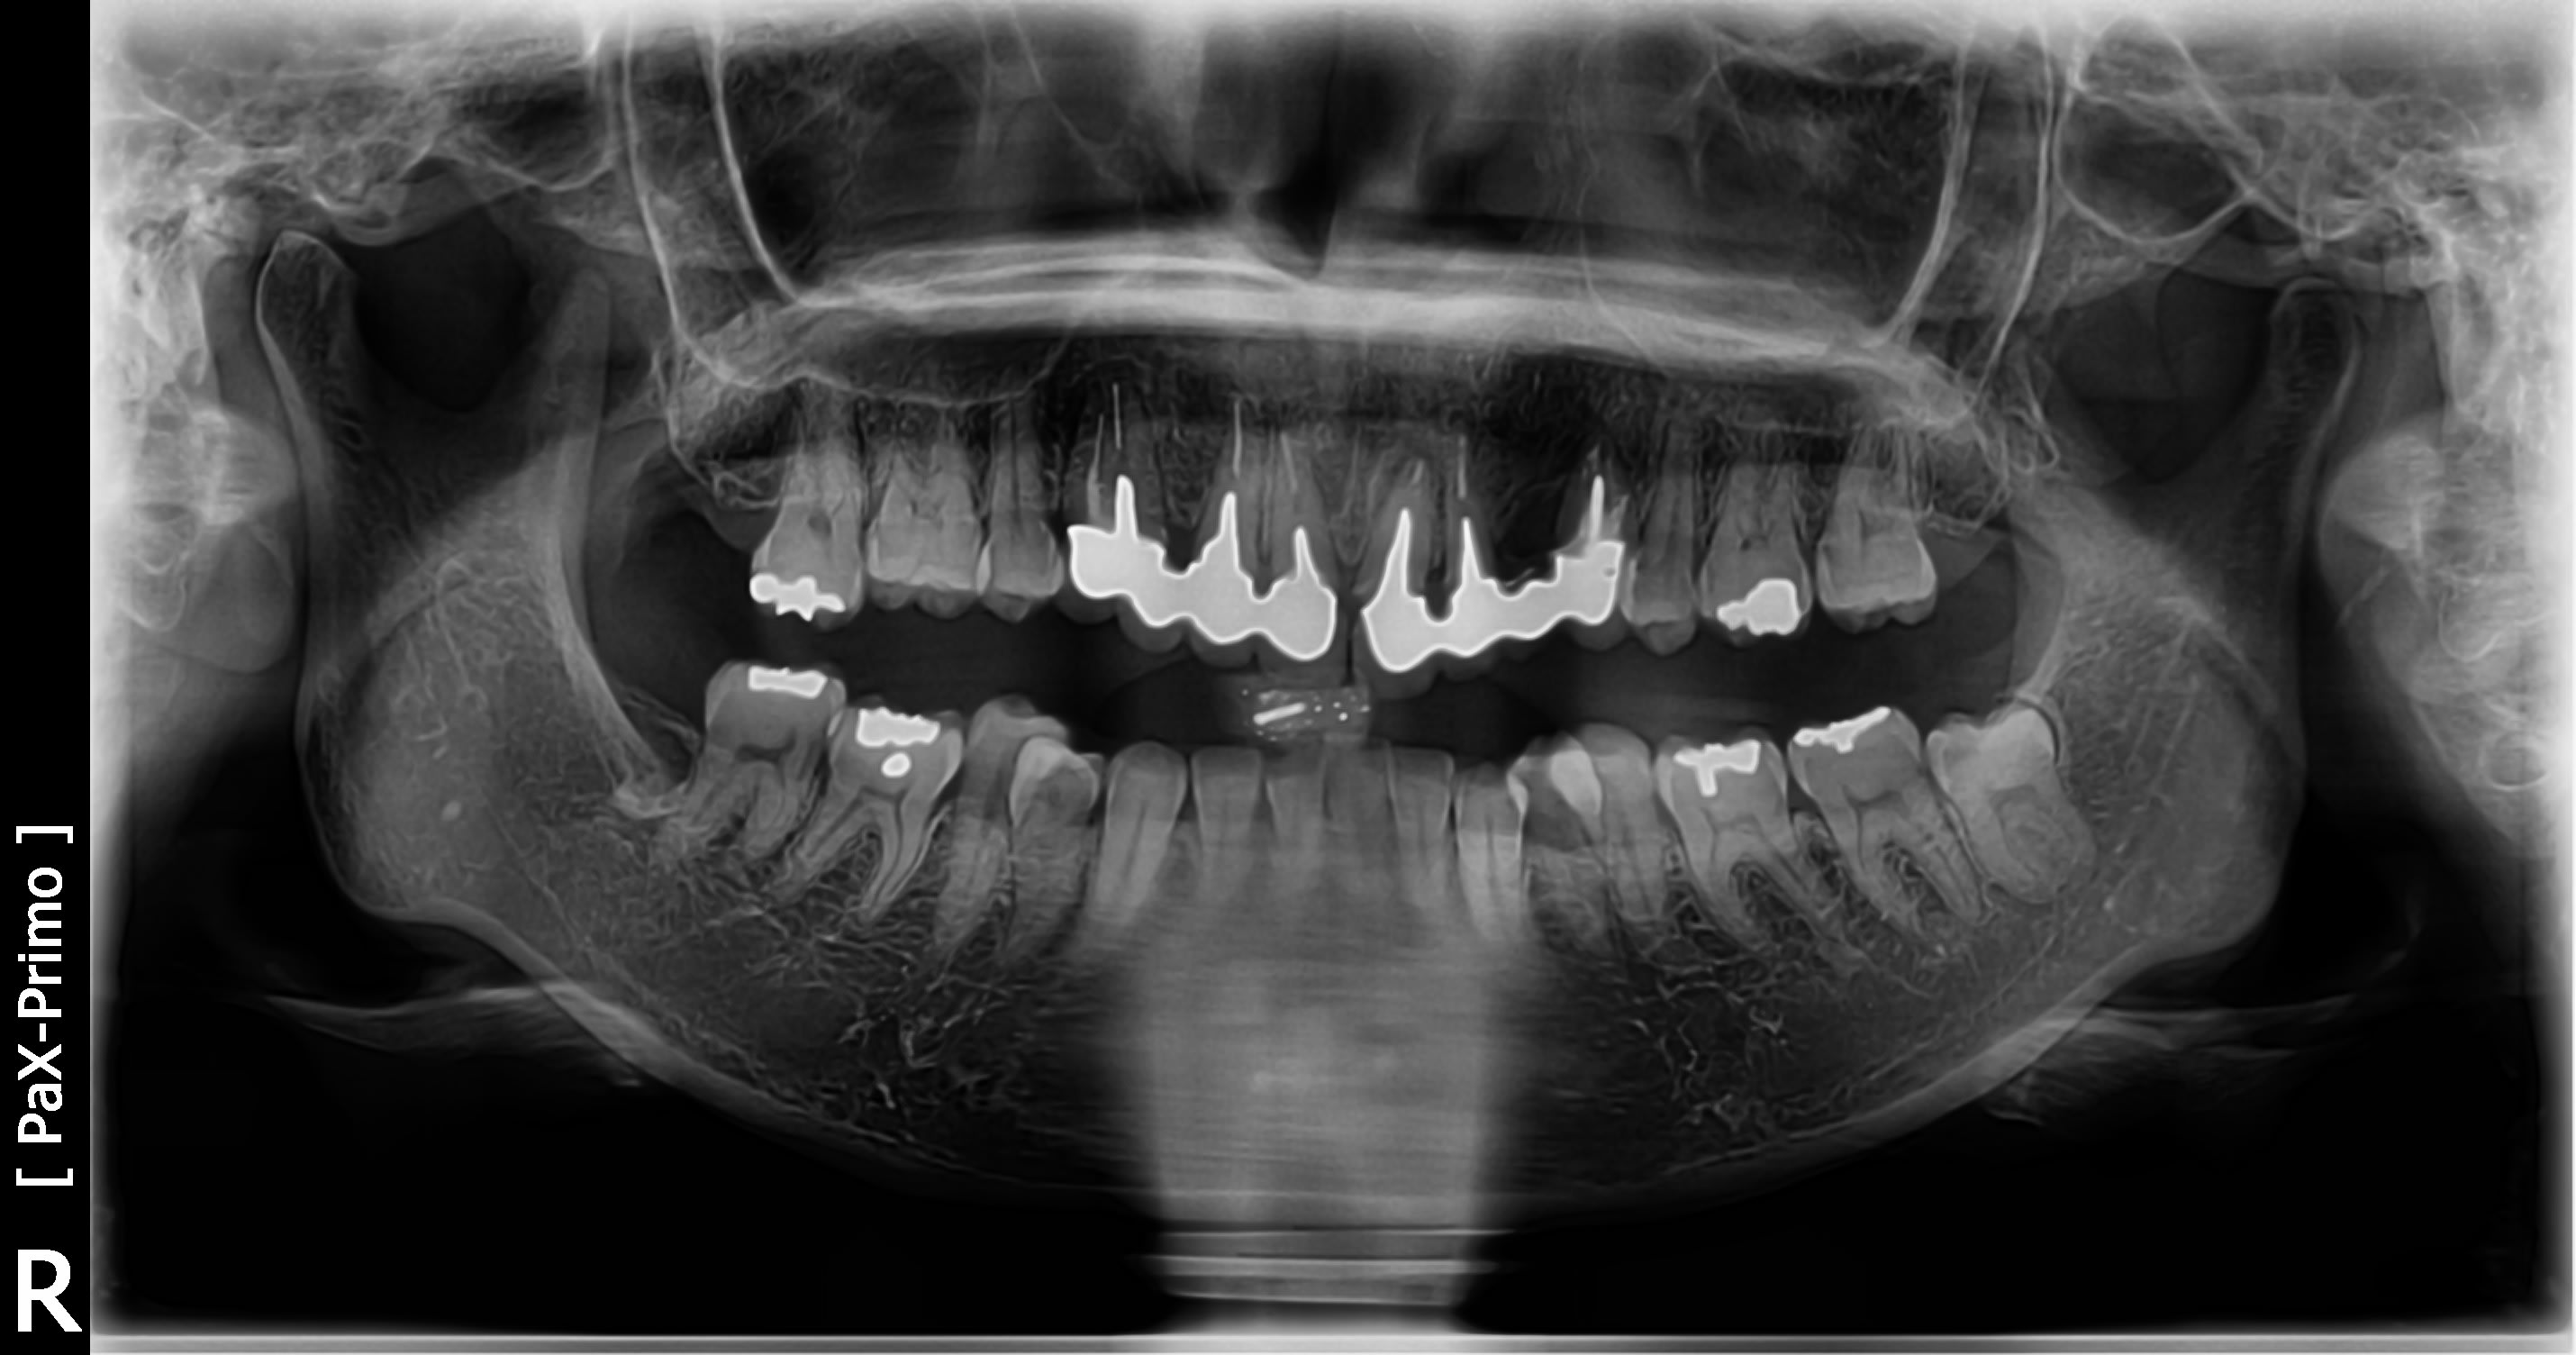

Voici une photo des incisives mandibulaires.

Assez abrasees en effet.

La patiente va avoir besoin qu'on lui retire rapidement 24 qui a sa racine perforee en deux endroits.

merci matten de réactiver la discussion....

En resurvolant le cas, j'ai bien peur qu'il y ait une fissure radiculaire sur 21,( lésion très latérale tenon long e, descellement multiples, bras de levier à partir de 24 pilier destabilisé et déstabilisant du fait de la fracture radiculaire)

Integrer cette hypothèse dans un plan tt.(une retro de 21 svp)

Coucou tout le monde, j'ai recu les modeles de la patiente.

A savoir qu'en lateralite la fonction canine est a 100% et il n'y a aucun contact en lateralités sur les premolaires 35-45.

Si vous avez une idee du plan de traitement pour resoudre le probleme du bridge 21-22-24 qui est mort. (racine 24 a extraire). Implants 23-24 seront necessaires.